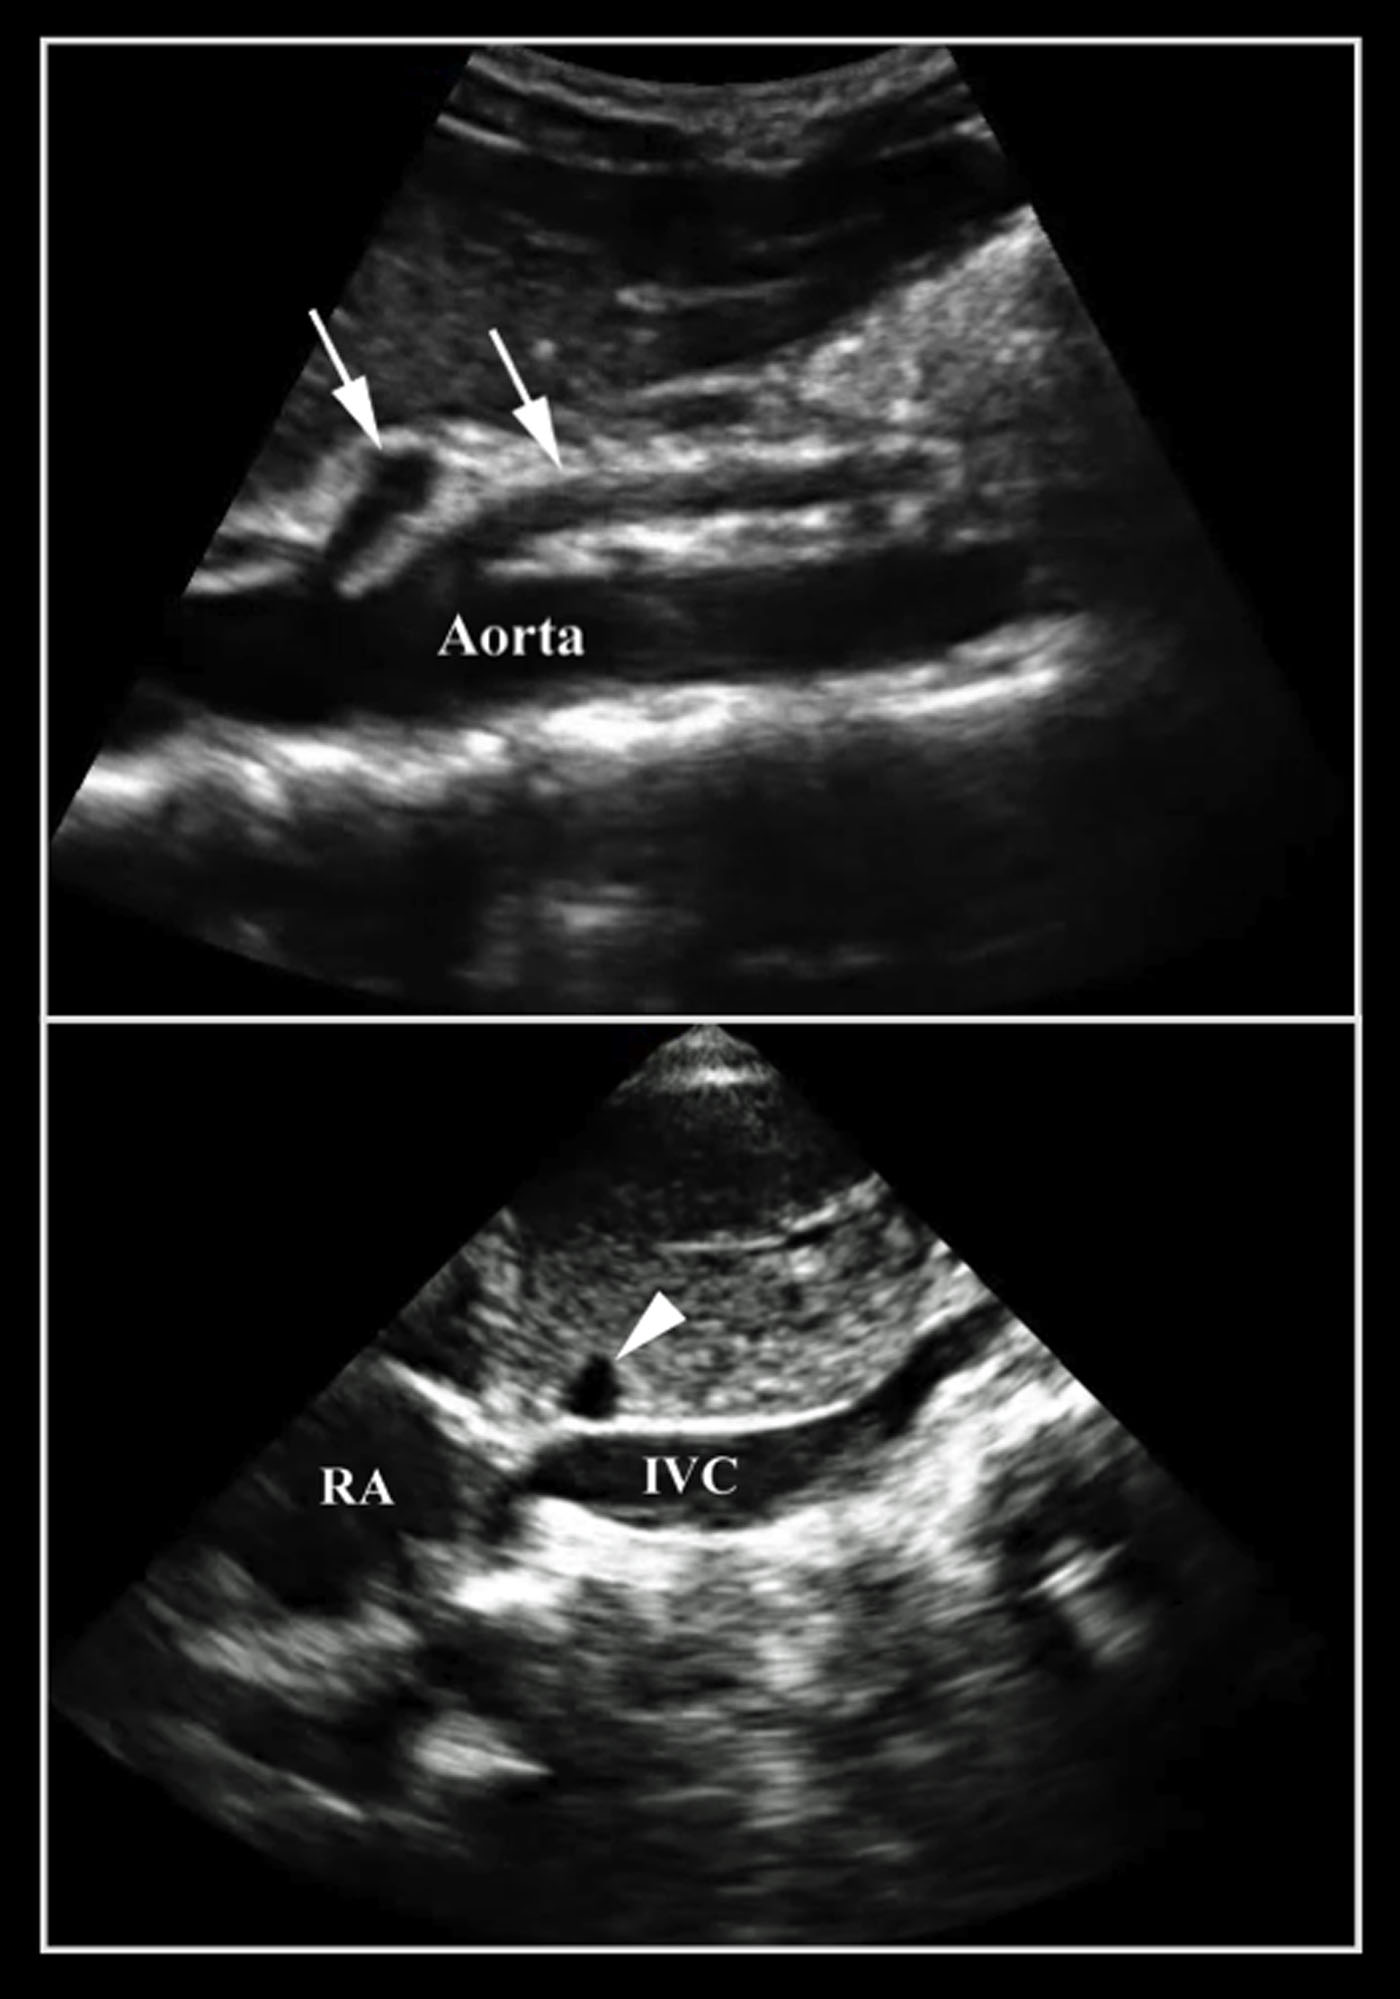

- Do not mistake the IVC for the aorta. It is important to identify the branches of the aorta. The IVC will run through the liver with the hepatic vein draining into it. You can also identify the IVC entering into the right atrium (Figure 9).

- Figure 10. Note the difference between the aorta and the IVC